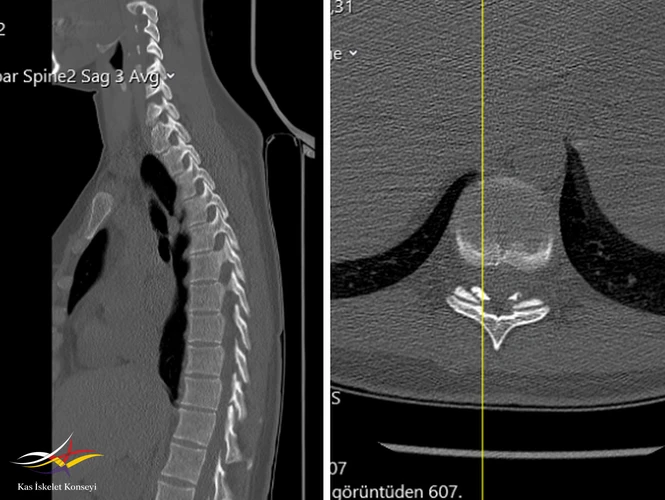

İncelemeler: HLA B27 negatif. Torasik MRG: Alt dorsal seviyede disk hernisi mevcut. Belirgin bir nöral bası yok.

Sırt ağrısını açıklayacak başka bir neden bulunamaması nedeniyle, tek seviyede saptanan bu alt torasik dejenere disk seviyesinin semptomların kaynağı olduğu düşünüldü. BT'de bu seviyede saptanan ligamentum flavum kalınlaşmasının bu seviyedeki mekanik yüklenme ve anormal biyomekaniğin bulgusu olduğu düşünüldü. Tanı tedavi amaçlı faset + epidural enjeksiyon planlanabileceği; egzersizin ve korse kullanımının uygun olduğu; ağrının tüm bu konservatif tedavilere yanıt vermemesi ve günlük hayatı etkileyecek seviyede olması durumunda son seçenek olarak basit diskektomiden ziyade bir stabilizasyon operasyonuna gidilebileceği tartışıldı.